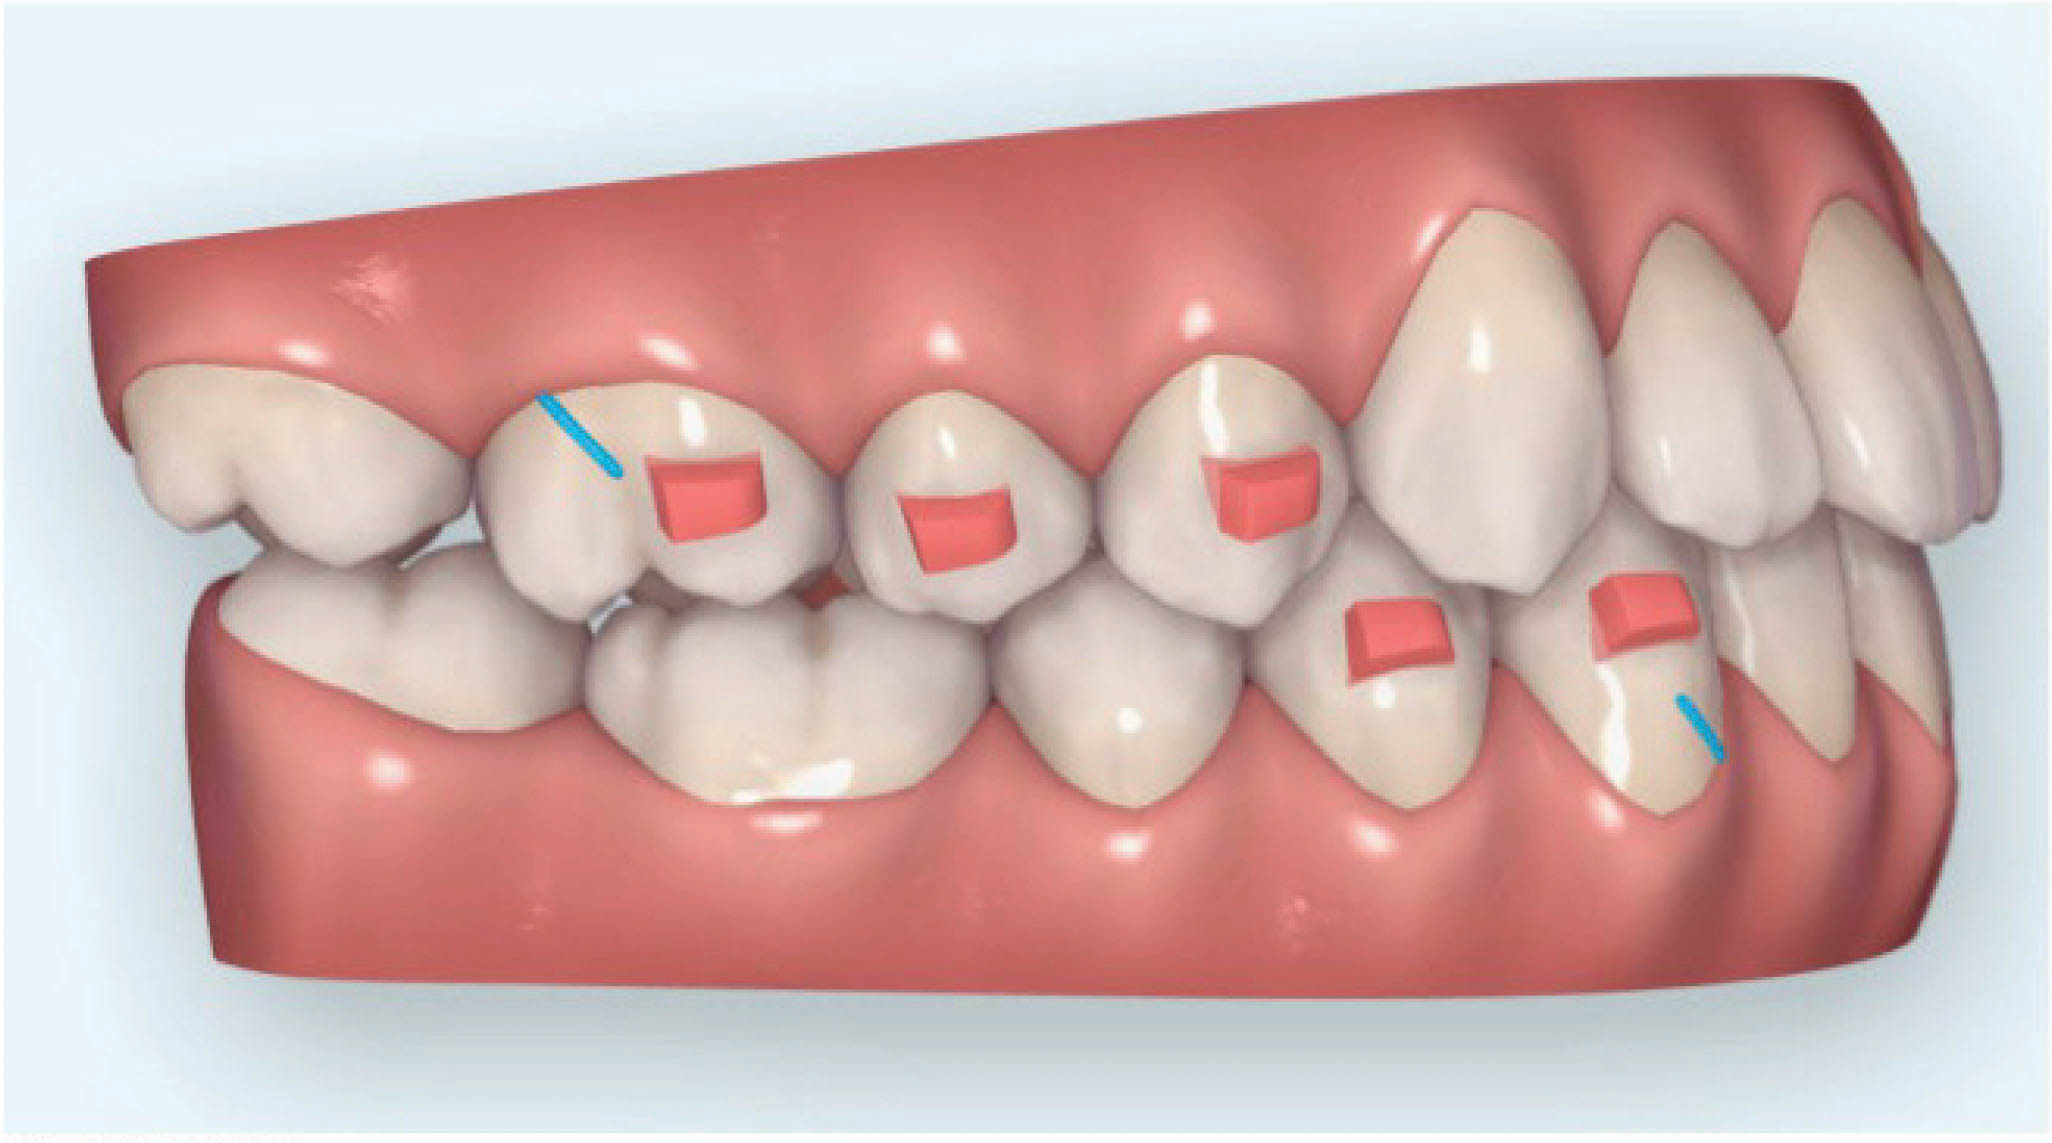

دیستاله نمودن دندانهای خلفی بالا با الاستیک ۴ انسی را در نظر داریم تا هم رابطه مولری و کانینی کلاسI بشوند و هم فضا برای لترال بالا درست شود.

بخاطر دیستاله شدن خلفیها احتمال مزیاله شدن قدامیها وجود دارد، لذا باید حتماً الاستیک کلاسII بدهیم تا مانع این اتفاق بشویم. وقتی یک دندان ۵۰ درصد دیستاله شدن خود را طی میکند، نوبت دندان بعدی جهت دیستاله شدن میشود.